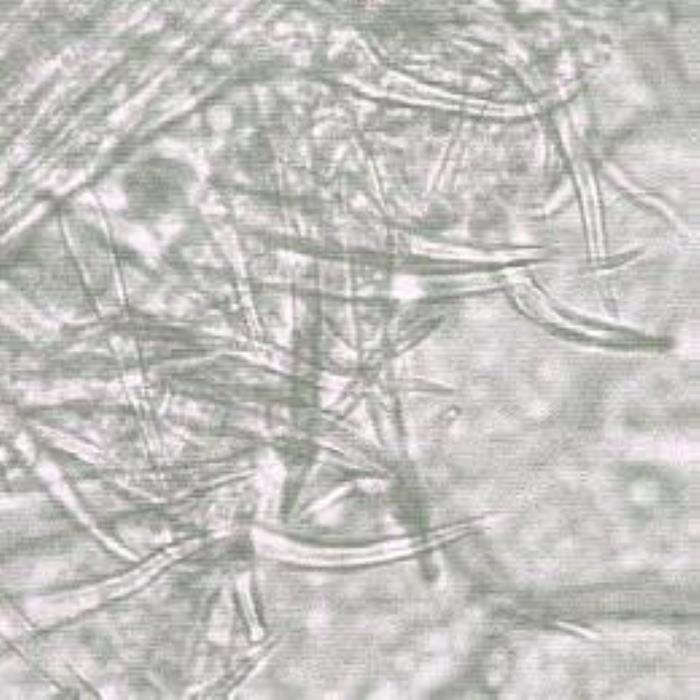

- (c). Surface view of the lower epidermis of the leaf showing dense conical, tapering or a little curved covering trichomes on the epidermis near to a main vein (Magnification: x 400, x 250 and x 250, respectively).

A transverse section of the leaf shows a unilateral structure. The upper epidermis is covered with a thick striated cuticle. The epidermal cells are colourless, anticlinal mostly oblong but round cells also exist. Some epidermal cells also extend to form papillose cells or short covering trichomes. Few longer conical trichomes are also observed. The mesophyll palisade tissue consists of one layer of oblong compactly arranged cells with straight cell walls. They are smaller in size compared to the upper epidermal cells and they are rich in chlorophyll and some small-sized coloured crystalline substances. The spongy mesophyll cells are small, round or oblong compactly held cells. Some of those cells adjacent to the palisade cells contain large rosettes of calcium oxalate crystals. The other cells contain coloured materials, large brown crystalline substances and prisms. The mesophyll spongy cells are traversed by vascular strands containing spirally thickened vessels. The lower epidermal cells are small oval periclinal cells covered with a thick striated cuticle. Unicellular conical covering trichomes a are more observed on the lower epidermis with their round basal cells. Also, clavate glandular trichomes are observed on the lower epidermis. Stomata are oval, anomocytic and they are well-distributed on both epidermises (DPS, ZCHRTM unpublished results).